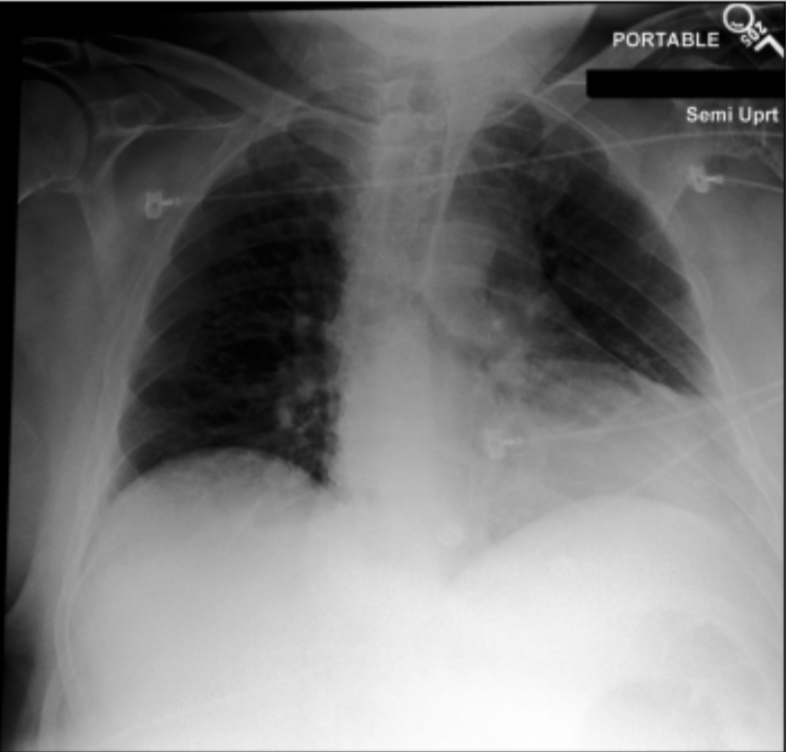

4.3.3 Visual grounding

In this section, we evaluate RadVLM’s visual grounding capabilities, which could help clinicians localize specific regions or pathologies on a CXR. This is particularly useful once a pathology has already been identified – either by a radiologist’s input or through our previously described AI tasks – since it allows one to pinpoint exactly where the abnormality appears on the image.

We report performance metrics for the three main grounding tasks RadVLM was trained on: anatomical grounding using the Chest Imagenome test set, abnormality grounding using the VinDr-CXR test set, and phrase grounding using the MS-CXR test set (Table 1). For each task, we use mean Average Precision (mAP) as our primary evaluation metric.

Our results show that RadVLM performs well at localizing anatomical regions (e.g., “right lung”, “aortic arch”, illustrated in Figure 5a), achieving a mAP of 85.8 %, by far surpassing the other CXR grounding models (Table 4). This advantage is partly explained by including the Chest Imagenome dataset (and thus the anatomical grounding task) in the training set, which CheXagent and MAIRA-2 did not leverage. However, it remains a key feature for any grounding model to possess a fine-grained understanding of CXR anatomy.

For the abnormality grounding task, RadVLM is less consistent (Figure 5b), likely due to higher sparsity of abnormality locations and labels, yet it still achieves best performance (Table 4). For the phrase grounding task, while MAIRA-2 and CheXagent demonstrate great performance, RadVLM surpasses them with a mAP of 81.8% (Table 4), presumably benefiting from the newly released PadChest-GR dataset (Castro et al.,, 2024) used for training.

Overall, these results show that our instruction tuning strategy for visual grounding (covering three essential tasks), combined to a modern VLM backbone, offers a promising avenue to help clinicians localize anatomical and pathological features during a CXR exam. Furthermore, providing fine-grained details within an LLM-generated output may also enhance the ability to answer grounded questions in a multi-turn setting, as we explore next.